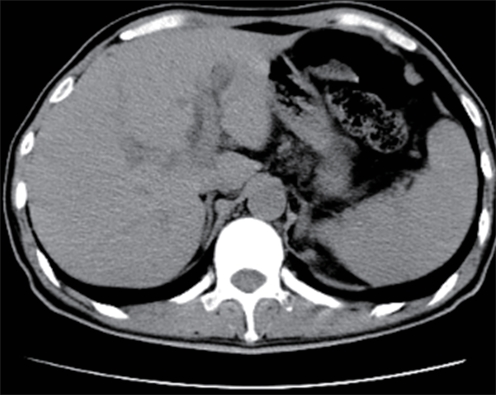

Value of internal stratification analysis of abdominal wall muscles in predicting complications after orthotopic liver transplantation

Xin SHI, Chongxiao LIANG, Bei ZHANG, Jiping WANG

2025, 41(2): 314-321. DOI: 10.12449/JCH250218

Abstract(741) HTML (353) PDF (3265KB)(54)

Abstract:

Objective  To divide the muscle into different subzones according to different density ranges using the stratified analysis on the basis of myosteatosis, and to investigate the effect of muscle density changes on complications (Clavien-Dindo grade ≥Ⅲ) after orthotopic liver transplantation (OLT).  Methods  A retrospective analysis was performed for the medical records of 145 patients who underwent OLT in The First Hospital of Jilin University from May 2013 to September 2020, and with the plain CT scan images of the largest level of lumbar 3 vertebrae of each patient as the original data, Neusoft Fatanalysis software was used to measure related muscle parameters. The independent-samples t test was used for comparison of normally distributed continuous data between two groups, and the Mann-Whitney U test was used for comparison of non-normally distributed continuous data between two groups. The chi-square test or Fisher test was for comparison of categorical data between two groups. RIAS software was used to extract clinical features and perform analysis and modeling, and three machine learning models of logistic regression (LR), support vector machine (SVM), and random forest (RFC) were constructed. The receiver operating characteristic (ROC) curve, the calibration curve, and the decision curve were plotted for each model to calculate the area under the ROC curve (AUC), sensitivity, specificity, precision, F1 score, and accuracy.  Results  The three machine learning models of LR-C, SVM-C, and RFC-C were established based on the 7 clinical features before muscle stratification analysis, among which the RFC-C model had an AUC of 0.803, a sensitivity of 0.588, and a specificity of 0.778 in the test set. Among the models of LR-CS, SVM-CS, and RFC-CS established based on the 16 clinical features after muscle stratification analysis, the LR-CS and SVM-CS models had an AUC of 0.852 in the test set, with a sensitivity of 0.765 and 0.706, respectively, and a specificity of 0.889 and 0.926, respectively. Comparison of the AUC, sensitivity, specificity, precision, F1 score, and accuracy of each model in the test set before and after muscle stratification analysis showed that there were improvements in the parameters of the predictive model after muscle stratification analysis. Comparison of the decision curves and calibration curves of each predictive model showed that the LR-CS and SVM-CS models had good efficacy in predicting postoperative complications (Clavien-Dindo grade≥Ⅲ) in OLT patients.  Conclusion  On the basis of myosteatosis, the division of the muscle into different subzones according to different densities using the stratified analysis has a certain value in predicting postoperative complications in patients with OLT.